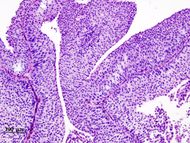

| Histopathology of urothelial carcinoma of the urinary bladder. Transurethral biopsy. H&E stain. | |

90% من حالات سرطان المثانة هي Transitional cell carcinomas (TCC) التي تنشأ من البطانة الداخلية للمثانة المسماة urothelium. العشرة بالمائة الباقية من الأورام هي squamous cell carcinoma, adenocarcinoma, sarcoma, small cell carcinoma وتراكمات ثانوية من سرطانات أماكن أخرى بالجسم.